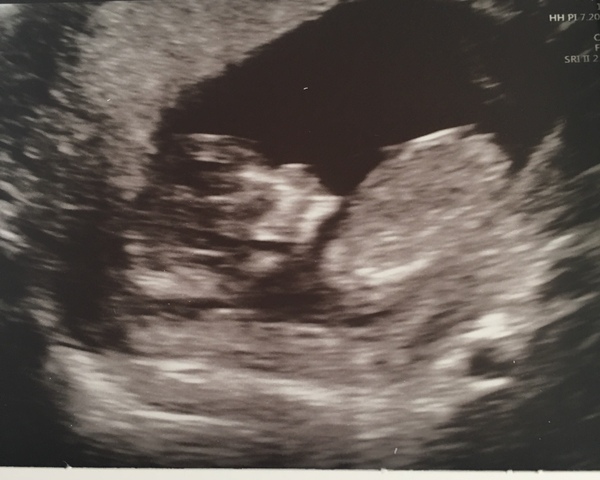

This is my 12 week scan. Off for my 20 week this week. Husband doesn’t want to know sex but I do! Just wondered if anyone had any guesses on gender and a reason why?

Was is a boy?? Just trying to get a hang of the theories- let me know if I was right or wrong! Hope you’re doing well xx